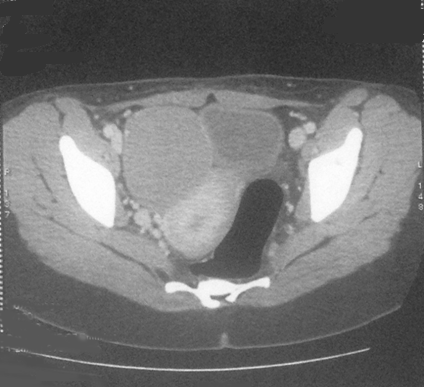

Five years later, she presented with abdominal pain. Computed tomography scan shows a 75 mm right adnexal mass evoking a cystic recurrence (Figure 2). The serum rate of anti-müllerian hormone (AMH) was elevated and measured 325 ng/ml. CA-125 rates were less than 35 UI/ml. In order to investigate PJS, a colonoscopy was performed and showed recto-colic polyposis. Mammogram showed benign cystic lesion of the breast. Papa smear did not show any abnormal cells. Radical surgery was recommended but the patient refused because of her will of childbearing. Laparoscopic exploration found a right adnexal cystic mass (Figure 3), with no evidence of ascites or peritoneal carcinosis. We underwent a cystectomy; leaving an ovarian tissue. The histologic findings showed circumscribed columnar epithelial nests composed of ring shaped tubules, which are encircled by hyalinized basement membrane-like material and concluded for a recurrent SCTAT. No mitotic count was reported (Figure 4) and (Figure 5). One month after surgery, hormonal rates were measured after ovarian stimulation and did not show hormonal activity. Fertility preservation attempt was a failure and the patient is proposed for a complementary surgery.

Figure 2: Computed tomography scan showing 75 mm right adnexal mass.